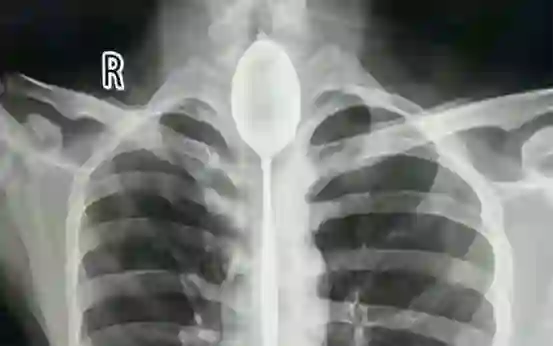

勺子卡食道一年

新疆煤矿总医院

2017年,20岁出头的张先生与他人喝酒打赌,冲动之下,将20厘米长的钢勺吞进肚里,勺头卡在了食道狭窄处。一年的时间里,张先生觉得并无大碍没有去医院将钢勺取出。

直到今年10月下旬,张先生被人在胸口打了一拳,感觉自己胸部疼痛、憋气、呼吸不畅,才去医院就诊。10月22日,新疆煤矿总医院的三位医生共同合作,冒着食道撕裂、穿孔、大出血、纵隔感染的风险,最终将钢勺顺利取出,为张先生免去了开胸取勺之痛。随后张先生顺利出院。